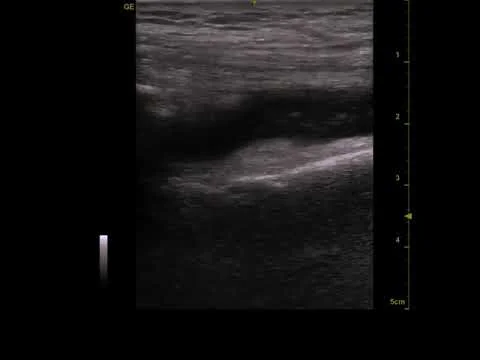

Small left knee effusion